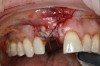

4. Facial and occlusal views of initial clinical presentation of tooth No. 8.

Figure 4

5. Facial and occlusal views of initial clinical presentation of tooth No. 8.

Figure 5